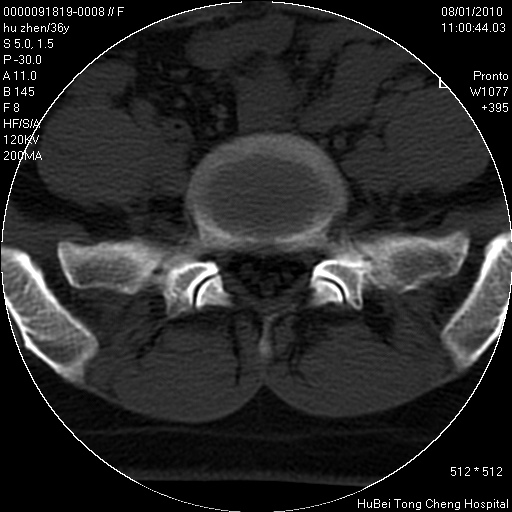

患者 女,36岁。右侧腰腿痛半月余。腰骶椎mr平扫偶然发现骶椎异常信号。

临床诊断:1)腰椎间盘突出症。2)骶椎肿瘤性病变?

骶椎ct平扫(层厚、层距均为5mm),图像如下:

考虑s1骨纤维异常增殖症。